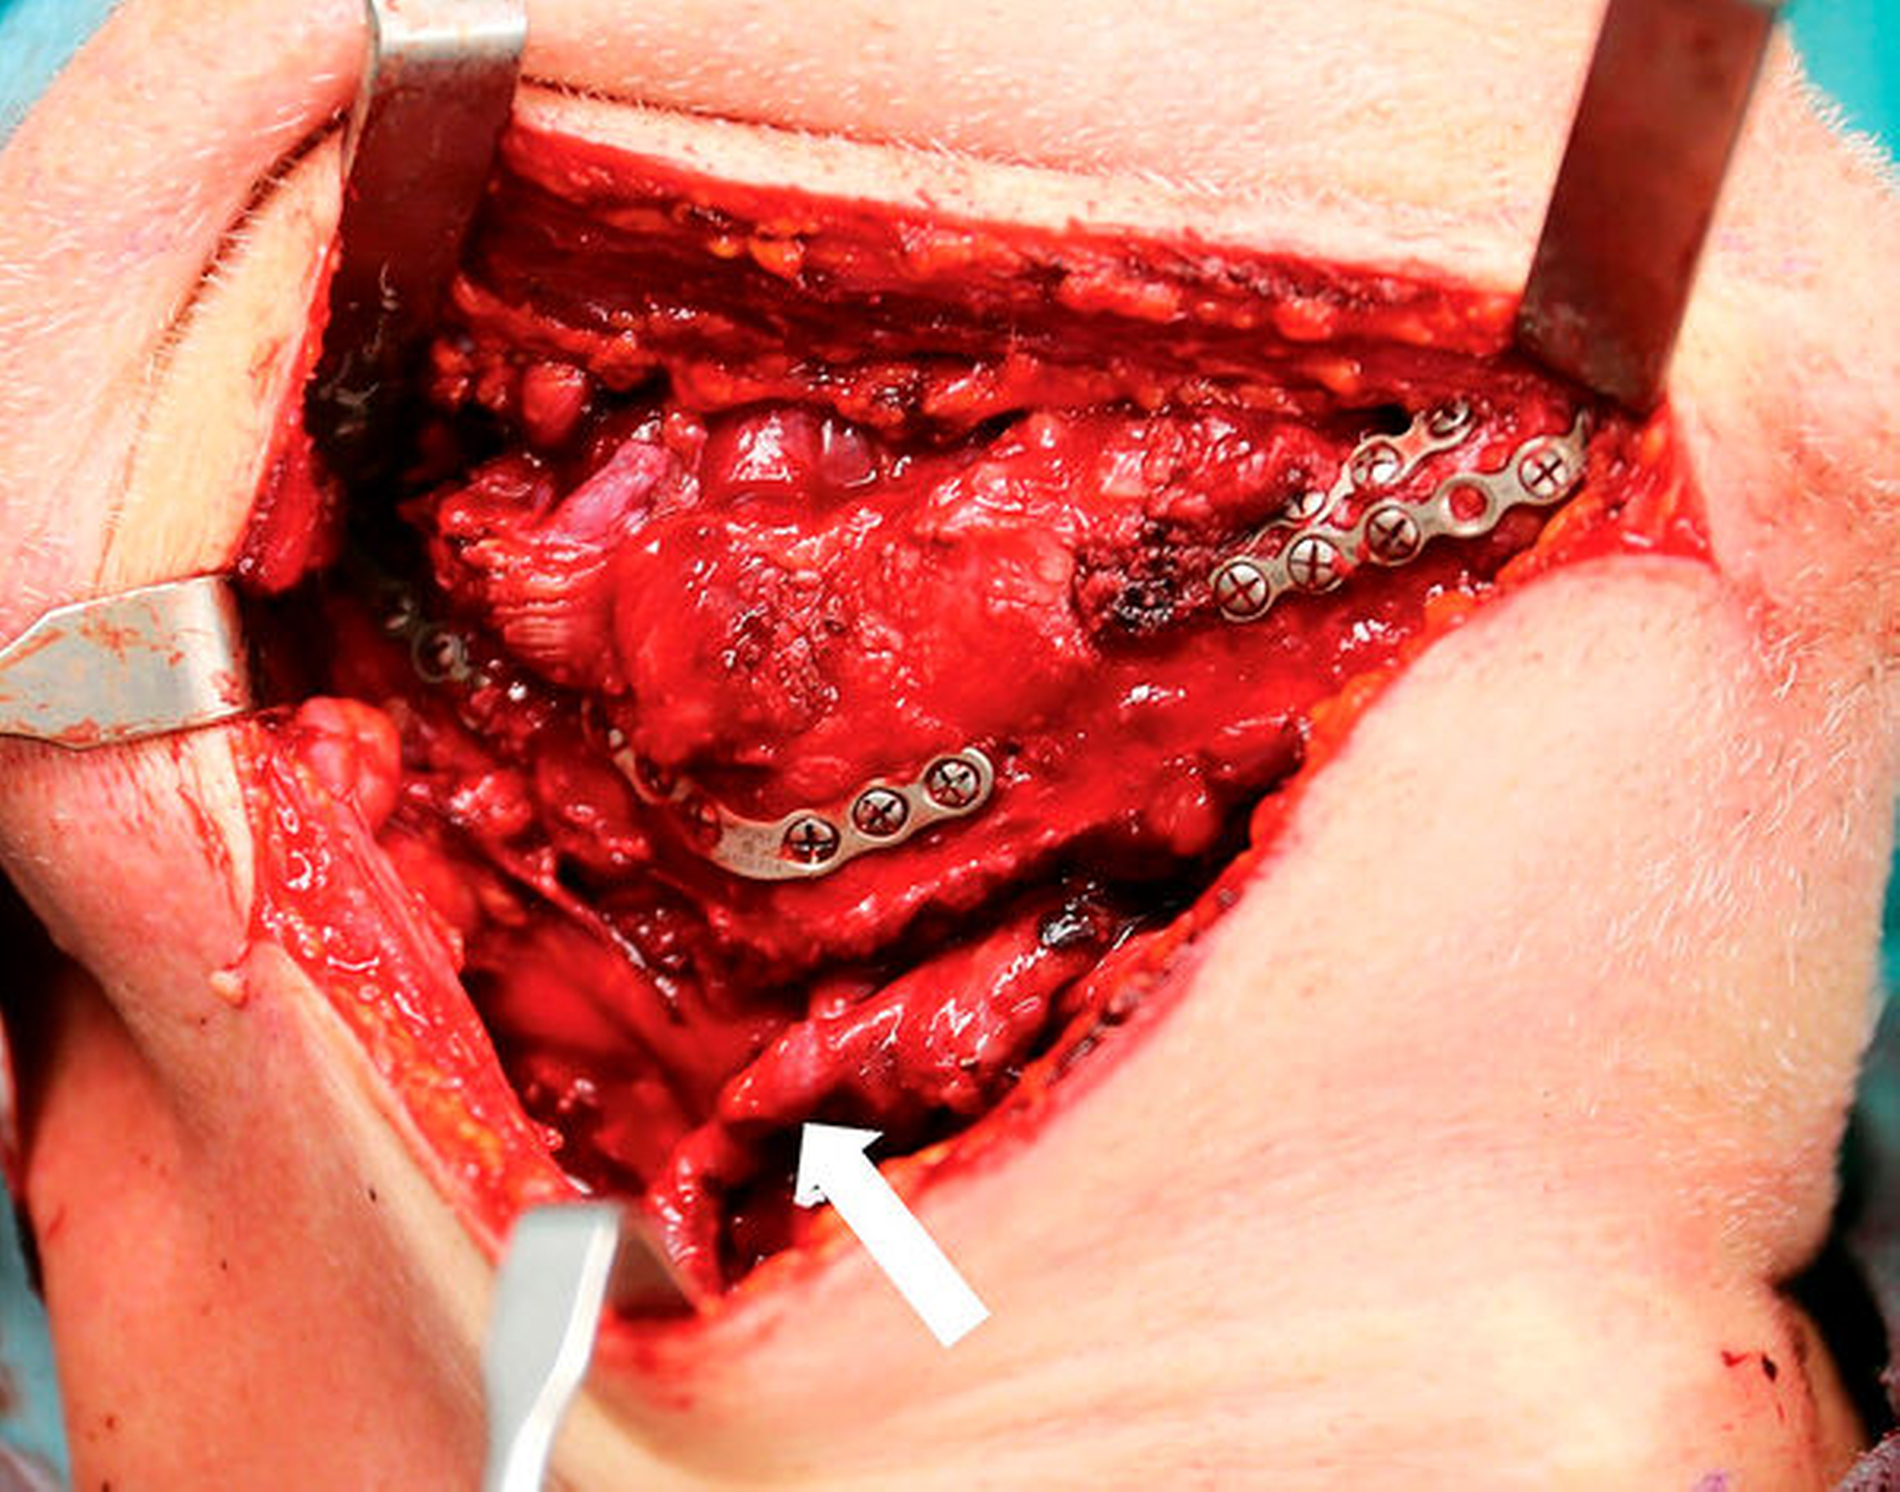

In Intubationsnarkose erfolgte nach temporärer Tracheotomie, zur Sicherung der Atemwege, die ipsilaterale selektive Neck-Dissection der Level I bis III mit anschließender schnellschnittkontrollierter radikaler Tumorresektion im Sinne einer Unterkieferkontinuitätsresektion. Die Osteotomien erfolgten dabei entsprechend der Cutting Guides. Abbildung 3 dokumentiert das resezierte Tumorhauptpräparat. Intraoperativ ergab sich kein Hinweis auf pathologisch verändertes Lymphgewebe, so dass auf eine Erweiterung der Neck-Dissection verzichtet wurde. Parallel zur Tumorresektion erfolgte unter temporärer Einbringung der entsprechenden Cutting Guides die Hebung eines zweisegmentalen Fibulatransplantats mit Hautinsel von rechts (Abbildung 4). Beide Segmente wurden vor der Transplantatabsetzung bereits osteosynthetisch verbunden. Das Transplantat wurde anschließend unter dem Operationsmikroskop mikrovaskulär an die rechte A. und V. facialis End-zu-End reanastomosiert.

Es folgten die passgenaue Einbringung des Fibulatransplantats in den mandibulären Defekt und die Fixierung mittels Osteosynthese (Abbildung 6). Die Hautinsel diente dem Verschluss des intraoralen Weichteildefekts (Abbildung 7). Der Wundverschluss der Donor Site erfolgte mit einem Vollhauttransplantat aus der Leiste mit Anbringung eines Überknüpfverbands.